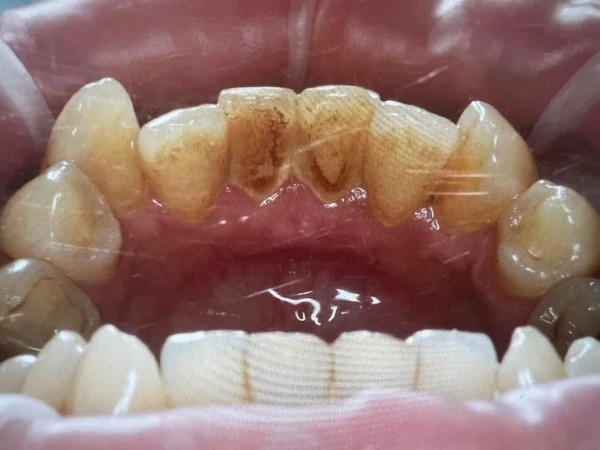

На снимке врач видит примерно такую картинку: чёрное облачко вокруг корня — это и есть периодонтит

Хронический апикальный периодонтит редко кто приходит лечить специально. Чаще всего его обнаруживают случайно: стоматолог делает рентген, а там — чёрное облачко вокруг корня зуба. Вот так он и выглядит.